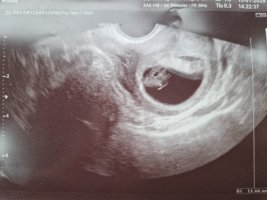

Nå er det ikke lenge til vi kan dra på ultralyd og se våre små frø. Kanskje det er hyggelig å samle litt bilder i en tråd?

Ble dessverre satt tilbake fra 6+5 til 6+0, noe som er litt rart med tanke på stabil syklus, men da tok det vel litt tid fra EL til befruktning.